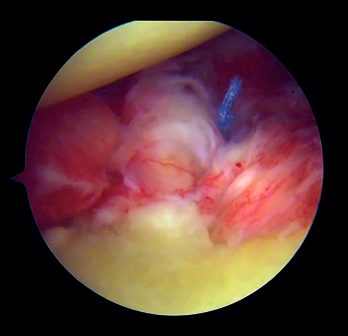

Capsulolabral repair (Figure 5)

After confirming the correct position and stability of the graft, capsulolabral tissues are repaired using glenoid implants, leaving the graft extra-articular.

Figure 5. View from the posterior portal (left shoulder). Capsulolabral repair by means of glenoid implants, leaving the graft in an extra-articular position.